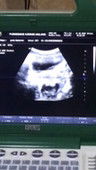

Ada nggak yang ngalamin 11 Minggu belum keliatan janin? Terus usia di USG beda sama hitungan hpht?

Baca lagialhamdulillah aku USG di 11minggu janin keliatan DJJ ada tp belum keliatan aktif tidaknya, bismillah semoga aja sehat semua diberi kesempurnaan tanpa krkuarangab suatu apapun